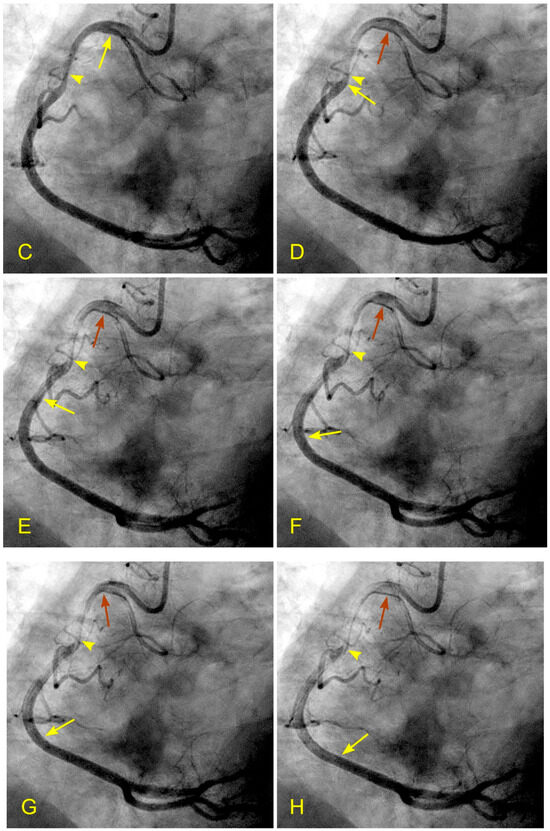

Figure 17.

(A,B) Antegrade flow in the right coronary artery (RCA). These images are in continuous sequence. (A) The artery is completely full of contrast in black. There is a severe 80% lesion in the mid-segment of the RCA (arrowhead). (B) In the ostium of the RCA, the blood, in white, moves in at the beginning of diastole (arrow). (C–F) Antegrade and retrograde flows in the right coronary artery (RCA). (C) Now, the blood, in white, continues to move in at the proximal segment of the RCA (arrow). (D) The blood, in white, reaches the center of the mid-segment where the lesion is located (arrowhead). The contrast looks darker. This is the interface location between the antegrade and retrograde flow at the transition from diastole to systole. (E) The blood, in white, reaches the beginning of the distal part of the mid-segment (arrow). At this location of the transition between systole and diastole, the contrast still looks dark (arrowhead). (F) The contrast looks darker in the mid-segment, and in the proximal segment, the contrast in black looks darker and is at a standstill (red arrow). (G,H) Antegrade and retrograde flow in the right coronary artery (RCA). (G) The blood, in white, reaches the beginning of the distal segment (arrow). At the location of the transition between systole and diastole, the contrast still looks dark (arrowhead). The contrast looks darker in the proximal segment, where the contrast in black is at a standstill (red arrow). (H) The blood, in white, reaches the middle of the distal segment (arrow). At the location of the transition between systole and diastole, the contrast still looks less dark (arrowhead). The contrast looks lighter in the proximal segment (red arrow).